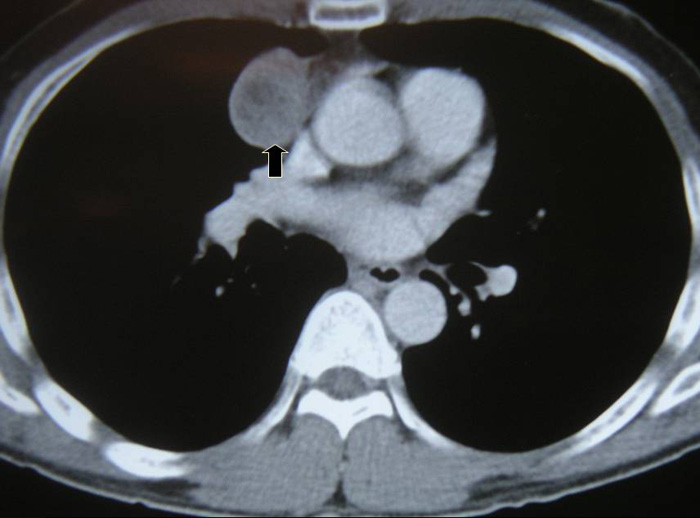

Larger well-encapsulated tumours, preferably less than 5cm, are also suitable for VATS provided the above surgical oncological principles are strictly adhered to (Figures 13 and 14, Video 6). Minimally invasive thymomas are tumours detected to have limited invasion of a segment of lung, pleura, phrenic nerve or pericardium at the time of VATS. The above described oncological principles are adopted here where the non-tumorous part of the gland is mobilized first followed by en bloc removal of tumour together with a cuff of involved pericardium, lung or phrenic nerve. In invasive thymomas division of the involved phrenic nerve and a wedge of lung are carried out early so it can be used for traction and grasping when dissecting the tumor last. This is done by creating a passage between the lung (usually the anterior segment of upper lobe) and tumour. An endostapler is then introduced through the 10mm port and the involved lung is wedged by passing the stapler through the created passage. The tumor is always dissected last, especially if it invades the pericardium, because on opening the pericardium the pulsating heart makes subsequent dissection of the gland and tumor difficult and hazardous (Video 7). Dissecting the tumor last also minimizes tumor handling and manipulation. If the tumor is dissected first, its weight will obstruct the surgical field, making subsequent dissection of the rest of the gland difficult and oncologically hazardous (Video 8).

The mean diameter of thymomas was 5cm (range 1-9 cm). A right sided approach was used in 79.3%. 30 patients were in Masoaka stage I, 34 in stage II, 12 in stage III and 1 in stage IV. The 13 stage III and IV patients were found to be locally invasive only at time of VATS. The mean diameter of minimally invasive thymomas was 34mm (range 23-55 mm). These cases had limited resection of involved structures (perithymic fat, cuff of pericardium, phrenic nerve and wedge of lung were removed en bloc with the tumour and thymus gland). To date all patients are alive with 2 local recurrences.